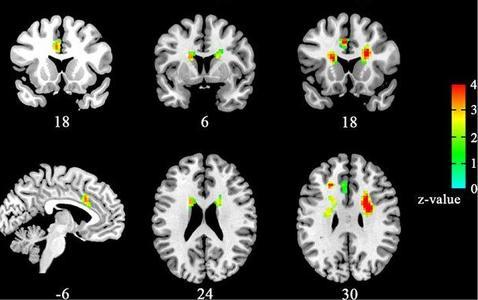

Para llegar a esta conclusión, el equipo utilizó técnicas de neuroimagen, en concreto imágenes de resonancia magnética funcional para examinar las diferencias en los patrones de conectividad cerebral en cien estudiantes universitarios. Los voluntarios se dividieron en tres grupos: los que estaban enamorados, los que habían dejado de estarlo y los «solteros».

Los investigadores encontraron en el grupo de los enamorados un aumento de la actividad cerebral en reposo en una zona llamada cortex del cíngulo anterior del hemisferio izquierdo, lo que sugiere que este área del cerebro está muy relacionada con el estado de enamoramiento.

Sin embargo, la actividad cerebral en otra área en la profundidad de los hemisferios cerebrales, el núcleo caudado bilateral, se redujo significativamente en el grupo de los que habían dejado de estar enamorados. Esta estructura del cerebro está asociada con la detección de recompensas, la expectativa, la representación de los objetivos y la integración de la información sensorial.

Curiosamente, los investigadores también encontraron en los enamorados una mayor conectividad entre el cortex del cíngulo anterior del hemisferio izquierdo con otras estructuras como el núcleo caudado, el núcleo accumbens o la ínsula, una red cerebral asociada igualmente con la recompensa, la motivación y la regulación emocional.